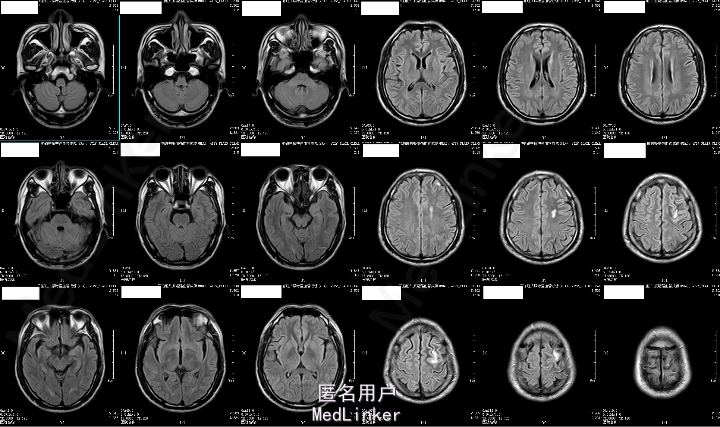

2015-05-26外院头颅MR:1.左额叶、枕叶病变考虑感染性病变可能性大(曼氏裂头蚴感染?)2.双侧上颌窦、筛窦慢性炎症。

2015-6-01我院头颅MRA:1.左侧额叶、枕叶及左侧基底节尾状核多发异常信号,考虑寄生虫感染(曼氏裂头蚴感染?)可能性大;2.左侧大脑前动脉A1段起始部稍狭窄;3.双侧筛窦炎症。

患者今年4月份时有吃“田螺、黄鳝”病史,既往有“高血压、糖尿病”,未规律治疗,结合其临床表现及头颅MRA“钻隧道”样改变,目前考虑“曼氏裂头蚴感染”可能性大。

成的中枢神经系统寄生虫病。I临床较为少见,易误诊。一般认为感染该病的途径有以下几种:食生或半生的蛙肉、蛇肉等(含裂头蚴);带有伤口的皮肤敷贴感染的生蛙皮、蛙肉等;饮用了含剑水蚤的生水。脑裂头蚴病的临床表现因感染部位的不同而各异。多以头痛、癫痫大发作及肢体活动障碍等为主,严重者可致颅内高压、视力损害、意识障碍甚至突然死亡。脑脊液检查可有蛋白及细胞数轻度升高。儿童脑裂头蚴病的病程一般不长,有些因虫体的迁延,其症状和体征也会发生改变。该病影像学表现多为单侧受累的单发病灶。病灶多位于皮质,也可侵犯脑室、脑干和小脑。活的虫体在脑内活动形成隧道、虫体分泌的产物及虫道周围的炎性反应使得该病影像学上具有一定特点:(1)主病灶一般较小,直径小于2 cm;(2)局部常伴发炎性反应,病灶周围脑实质可见不规则大片状水肿影;(3)MRI检查多表现为混杂长T1、长T2信号,临近侧脑室可变大,即所谓的“负效应”,增强扫描可见病灶呈匍行管状、串珠状、绳结状、扭曲条索状强化;(4)不同时期的影像学检查,病灶可在不同的部位;(5)CT检查可见点状钙化影,虽脑MRI对于钙化的显影不如CT,但也可表现出不均匀信号。脑裂头蚴病的病理学表现具有一定特点,裂头蚴幼虫在脑内迁徙游走形成坏死隧道,同时释放蛋白酶毒素溶解周围组织引起炎性反应,周围脑组织坏死后,局部炎性细胞浸润和纤维胶质细胞增生形成炎性肉芽肿。肉芽肿内可见有一条或数条虫体,虫体不分节,实体、无体腔,具有特征性的体壁结构是散在分布的椭圆形石灰小体及束状纵行肌纤维,前者可能为虫体的残骸。裂头蚴抗体血清免疫学检查(ELISA法)具有高度的特异性和敏感性。手术摘除裂头蚴为该病最有效的治疗手段,可

完整切除虫体及周围坏死的脑组织,但手术创伤性大。脑立体定向手术即可活检又可同时吸取虫体,创伤性小,尤其对于脑深部病变及重要功能区病变较为理想。单纯应用药物治疗,往往治疗不彻底、复发率高。本例患者病程较长,且经过多次驱虫治疗,脑组织病理检查见典型肉芽肿改变,中心坏死区可见到多个虫体坏死后钙化形成的石灰样小体,术后血清裂头蚴抗体阳性,进一步支持该诊断。术后经驱虫辅以激素治疗后获得了良好的临床治愈效果。该病常需与以下疾病鉴别:(1)结核瘤:是一种较少见的肺外结核。成熟型结核瘤病灶中心为干酪样坏死物,周围伴肉芽肿、炎性胞浸润及胶质细胞增生,增强扫描后也可呈结节样强化;但T2WI像呈典型的“环靶征”、伴有结核感染病史及中毒症状时有助于诊断。(2)脑肺吸虫病:肺吸虫成虫在脑内也可像裂头蚴一样迁徙游走,形成“隧道征”。但裂头蚴虫体较细长,“隧道征”较长而迂曲,更像缠绕的“绳结”;脑肺吸虫也可出现环形强化灶,但环影大小不一、聚而不连,常与肉芽肿结节并存。(3)脑囊虫病:为北方脑寄生虫病最为常见的一种,可为单发或多发的环形强化灶,直径约3~4 mm,其内可见点状头节,周围水肿常轻微,没有新旧病灶共存的特点。(4)脑肿瘤:脑肿瘤多有明显的占位效应;也可表现为环形强化灶,一般直径较大,且随病程有增大的趋势。而脑裂头蚴病可无占位效应,或表现为轻微的占位效应,甚至出现“负占位效应”;强化灶直径多小于2 cm,病变部位可迁徙变化,病灶无增大的趋势。(引用自 董秦雯,莫亚雄等,脑裂头蚴病一例并文献复习,中华神经免疫学和神经病学杂志[J],2014,21:94-97)